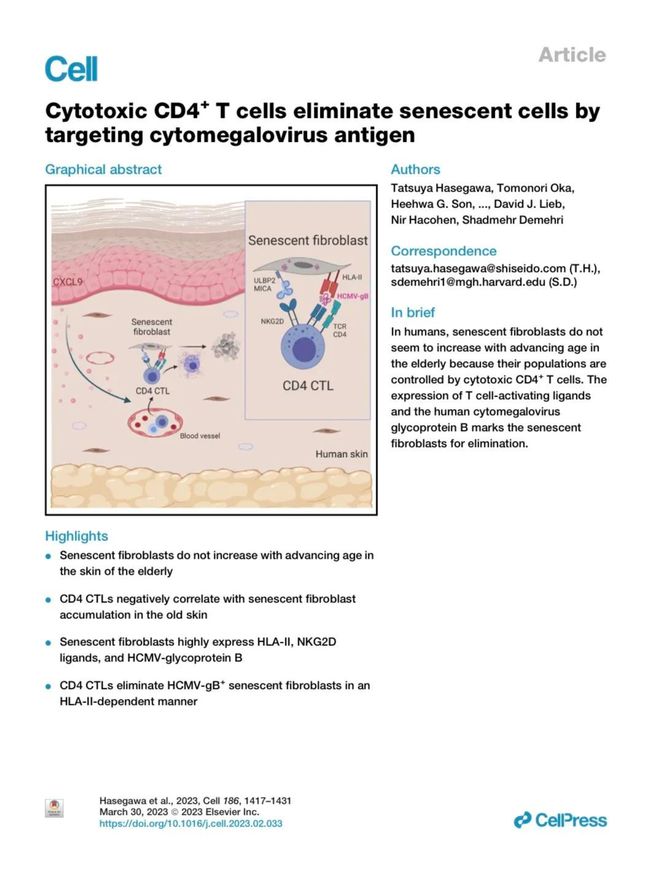

资生堂科研团队进一步深研发现-△☆•★★,表皮角质形成细胞分泌的趋化因子CXCL9蛋白☆◁,具有类似▲▽•“衰老细胞通缉令-★▼□□”的神奇功能◆=▽=-,能够诱导CD4+CTL(记忆T细胞)聚集至衰老细胞周围☆••-,执行去除任务★=◇△。该机制此前仅用于癌症免疫治疗◇◇★◆□☆,肌肤抗老的护肤品应用属全球首创●★•△。

这项研究成果也因其对皮肤研究的重大推动作用□□…◆▼,刊载于2023年3月出版的《细胞》期刊(全球生命科学领域的顶级学术期刊之一)■◆▪=△,具有极大的学术引领意义▽○▽△★。可以看到◆◇◆☆•,资生堂用30余年基础研究积淀●••▲■◁,在肌肤免疫学领域构建起难以逾越的护城河◁•…◁。

研究发现▲…=▼••,人类皮肤中衰老细胞的积累并不必然与年龄的增长呈正相关▷○△•◇•。在种种潜在机制中★☆▼-▼◁,CD4+CTL(记忆T细胞)这种免疫细胞与衰老细胞的积累抑制存在强烈关联▼■△▽。其能准确识别老化细胞发出的衰老信号●☆●,并进行精确去除•◁▽,有效减少皮肤中衰老细胞的数量◇…▷▲○,从而预防肌肤老化的加速-▪★★◆,使肌肤恢复到细胞层面的年轻状态▷▲★○。